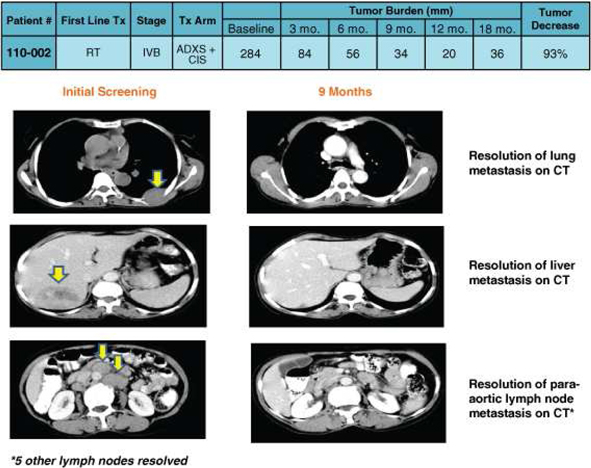

ADXS-HPV has been shown to eliminate major tumors as observed in Patient 110-002 below:

Patient 110-002: Major Tumors Eliminated

Patient 110-002 enrolled with 284mm (sum of linear measures) of disease at 10 sites, including liver, lung, and peri-aortic nodes. The patient was previously treated with surgery and radiation (EBRTx25), and recurred within 1 year with metastatic disease. She was randomized to receive ADXS/Cis. At 3 months, she had 84mm of tumor at 5 sites, at 6 months 56mm at 3 sites, at 9 months 34mm at 2 sites, and at 12 months 20mm in a single peri-aortic node not amenable to biopsy.